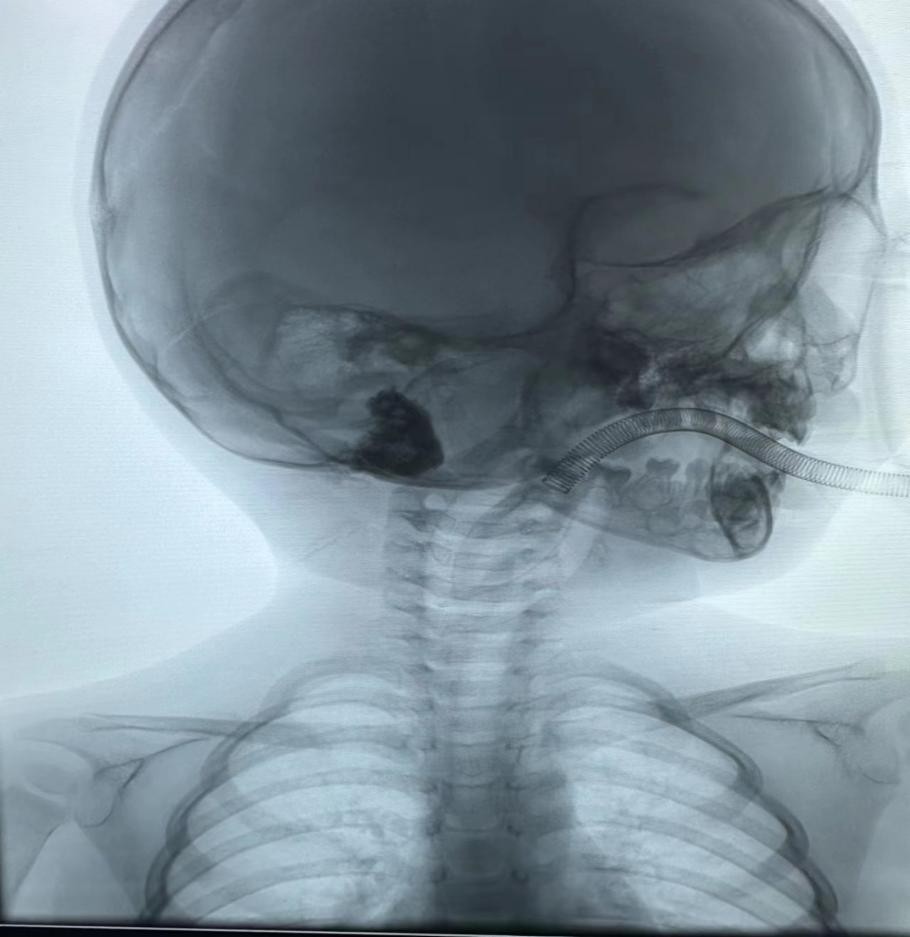

入院后,第二天即接受介入硬化治疗。消毒耳后皮肤,在超声及DSA引导下穿刺肿物,成功后用注射器抽出淋巴管液20ml,在DSA透视监视下经皮进行硬化治疗,完成后摄片,显示药液在瘤腔内沉积,手术结束,术中顺利。